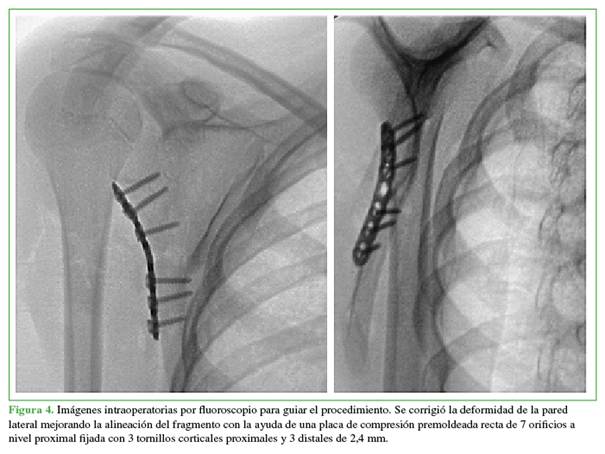

En las radiografías posoperatorias, se observó una alineación satisfactoria, con una reducción anatómica y posicionamiento del material de osteosíntesis. El cuerpo escapular fue reparado en su borde lateral, esto mejoró la estabilidad en el foco de fractura con la posición de la placa premoldeada. Se observó una mejor alineación gleno-humeral, logrando una restitución y un aumento del ángulo glenopolar, la corrección de la inclinación del segmento distal del foco de fractura y la alineación del cuerpo respecto a la radiografía lateral preoperatoria (Figura 5).

A causa de la condición social de la paciente, el primer control se efectuó a los 3 meses. La movilidad era adecuada, tenía una mejoría evidente en los arcos de movilidad pasivos asistidos y activos, una mejoría completa de la limitación funcional previa, con una adecuada apariencia posoperatoria y consolidación de la fractura en las radiografías de control, sin complicaciones, por lo que se consideró finalizar el seguimiento (Figura 6).